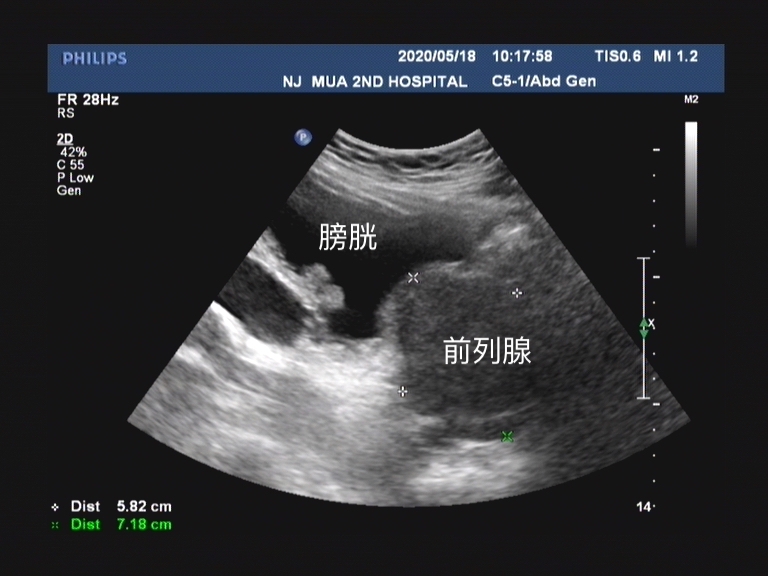

床位上有一位老爷子,今天来讲讲他的故事。事情是这样的,2年前老王因为排尿困难到外院就诊, 诊断为前列腺增生,于是接受了经尿道前列腺电切手术 。手术以后老王排尿困难的问题明显解决了,但就在这皆大欢喜的时刻, 老王在术后4个月再次出现排尿困难!

前列腺增生是泌尿外科的常见病、多发病,经尿道前列腺切除术已经成为治疗良性前列腺增生引起的下尿路梗阻症状的金标准手术方式。 但是无论医生的技术再高超,尿道狭窄往往是不能完全避免的,而且尿道狭窄已成为主要的晚期并发症之一。